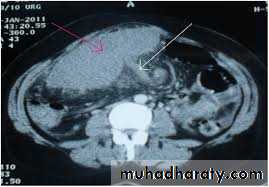

Ectopic (wandering) spleen

Ectopic (wandering) spleen is rare and occurs more commonly in women (7 : 1). It is due to lax attachments of the spleen to the retroperitoneum and long splenic vessels, such that the spleen 'wanders' the quadrants of the abdomen.,It may present acutely with abdominal pain due to torsion that may progress to infarction with hypersplenism (due to congestion), or simply with an abdominal mass with or without associated pain.

The diagnosis is confirmed by CT or duplex ultrasonography.

Treatment of ectopic spleen is by splenopexy (viable spleen) or splenectomy when the spleen is infarcted.

Ectopic spleen

Ectopic spleen by CT